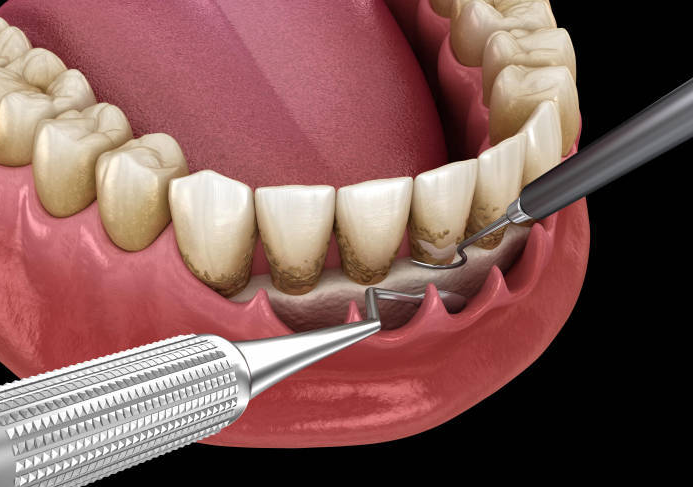

2、治療過程複雜

牙周病嘅治療唔係一個簡單嘅過程,通常要進行深層清潔,例如根面刮治同埋平整,仲可能需要藥物治療或者口腔衛生指導。有啲病人甚至需要進行牙周手術,例如翻瓣手術或者骨再生手術,每一步都需要高精準同專業操作。